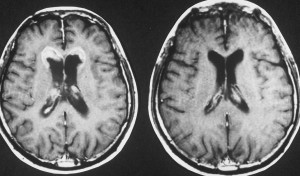

11歳(1977年)で発症して放射線治療を受け,21歳(1987年)で再発しました。側脳室の前角にガドリニウム増強される典型的なgerminomaの再発像がみれます。脳表にも脊髄にも髄液播種はありませんでした。

CDDP/VP-16化学療法で腫瘍は消失し,放射線治療を加えました。

2度目の再発です。側脳室の壁に再発したので,また化学療法をしましたら,右の画像のようにきれいに消えました。この時点でも髄液吸収障害性水頭症にも閉塞性水頭症にもなっていません。

3度目の再発です。また脳室の壁から再発しました。化学療法で腫瘍はまた消失しました。その後も維持化学療法を行ったのですが,脳室内再発が止められず,第4脳室底部の腫瘍が延髄に浸潤して死亡しました。

最後まで水頭症はありません。